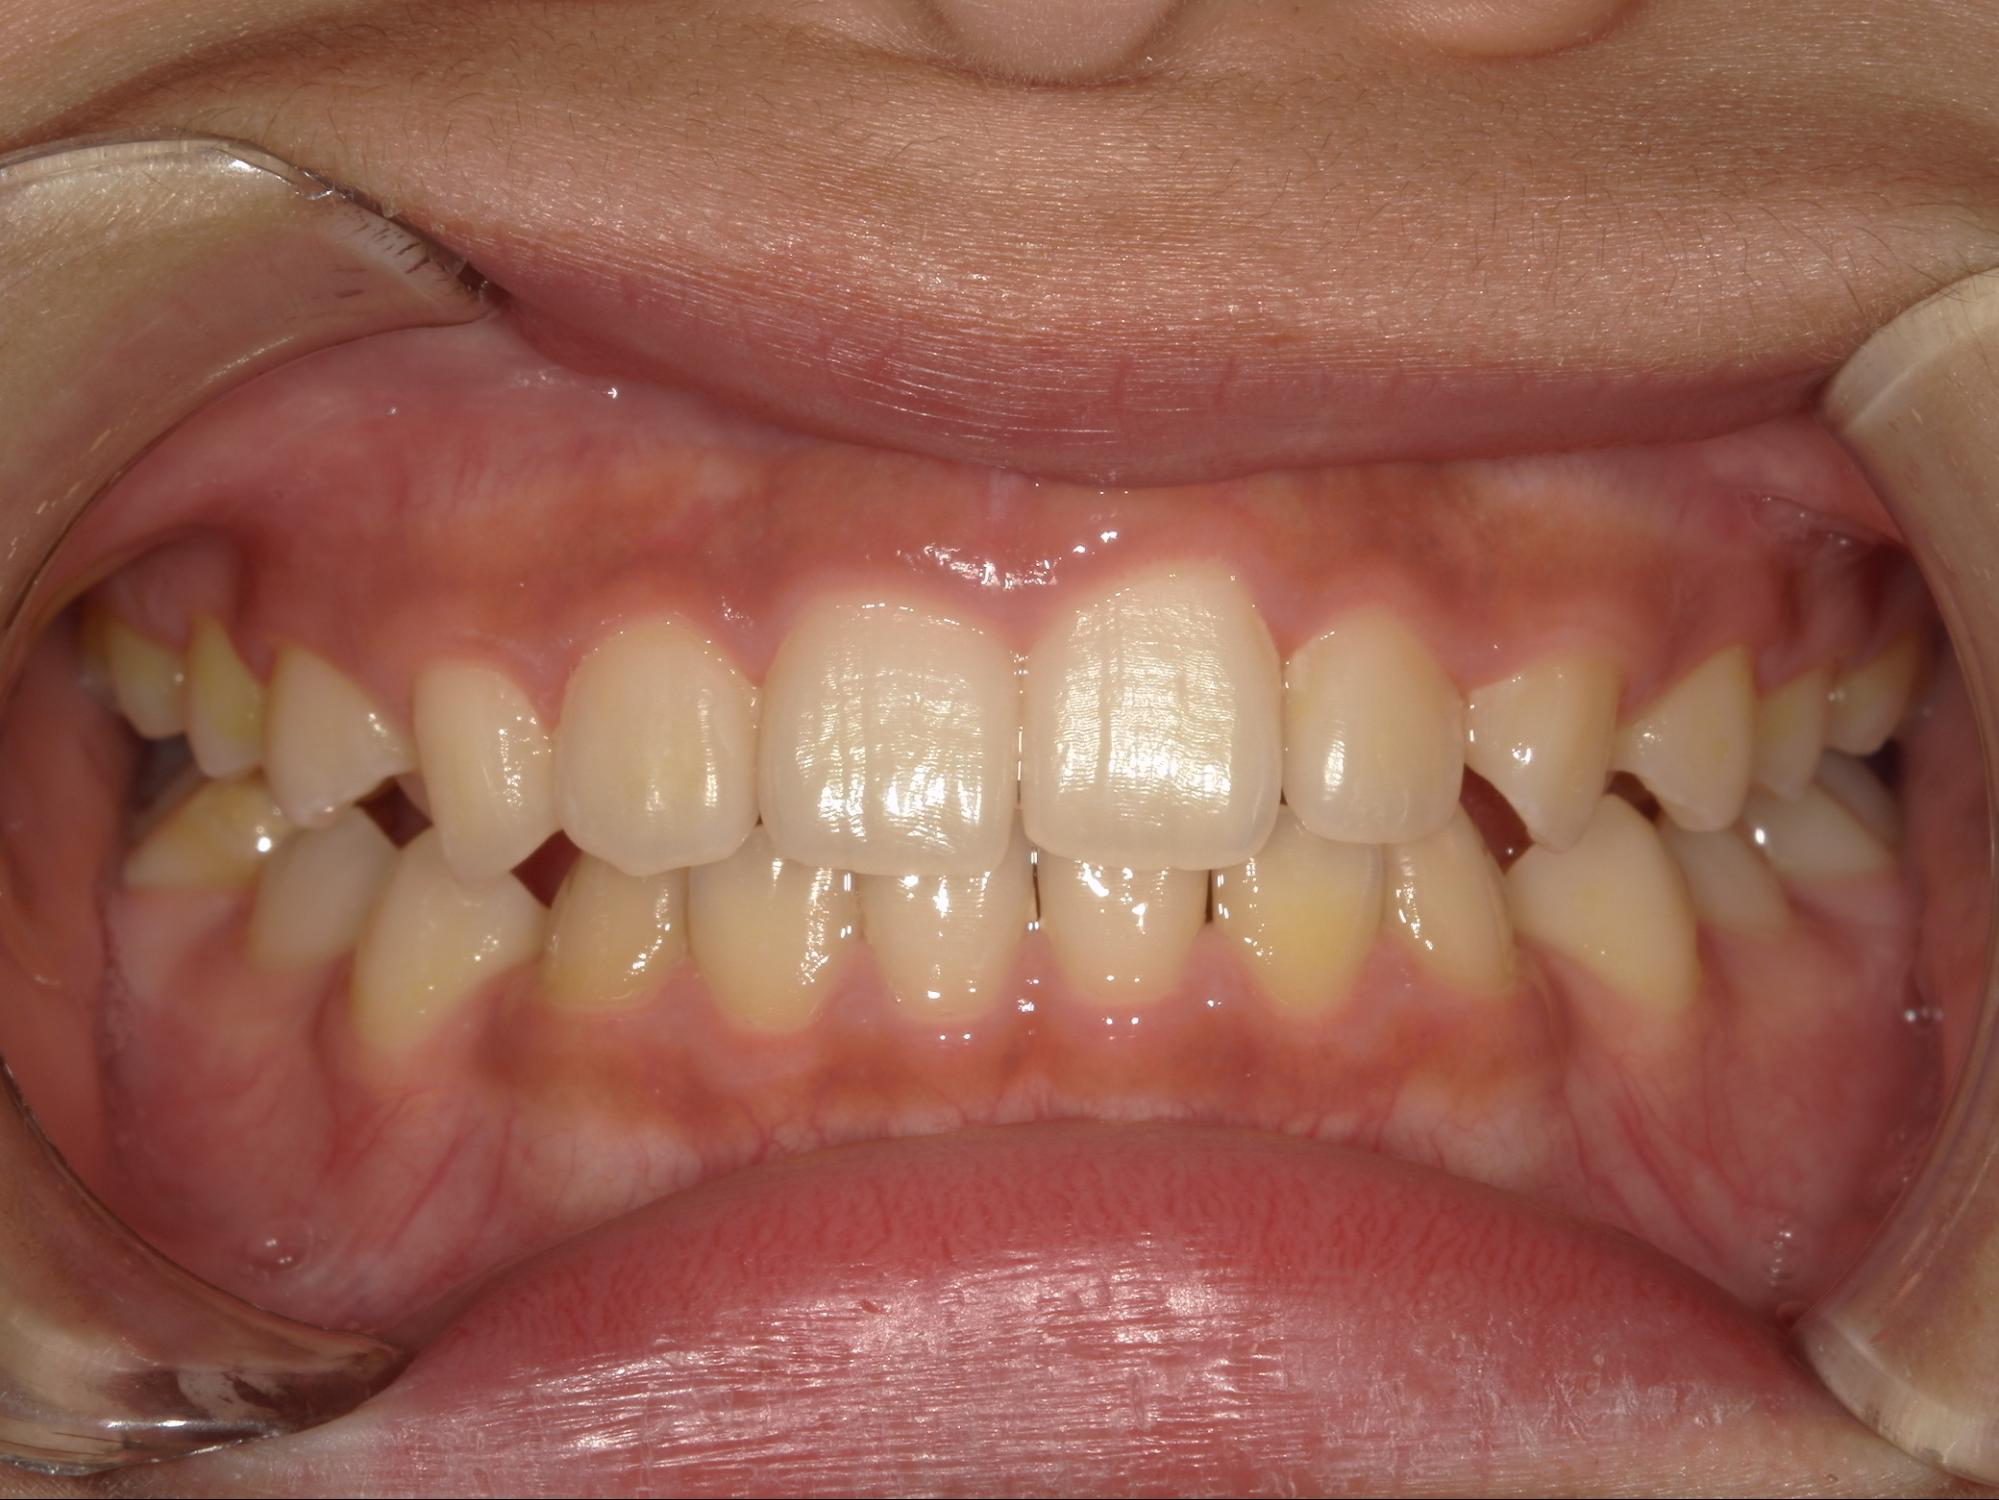

| 年齢・性別 | 男性 |

|---|---|

| 主訴 | 歯並びが気になる |

| 治療期間・回数 | 1年間 |

| 費用 | 330,000円(税込) |